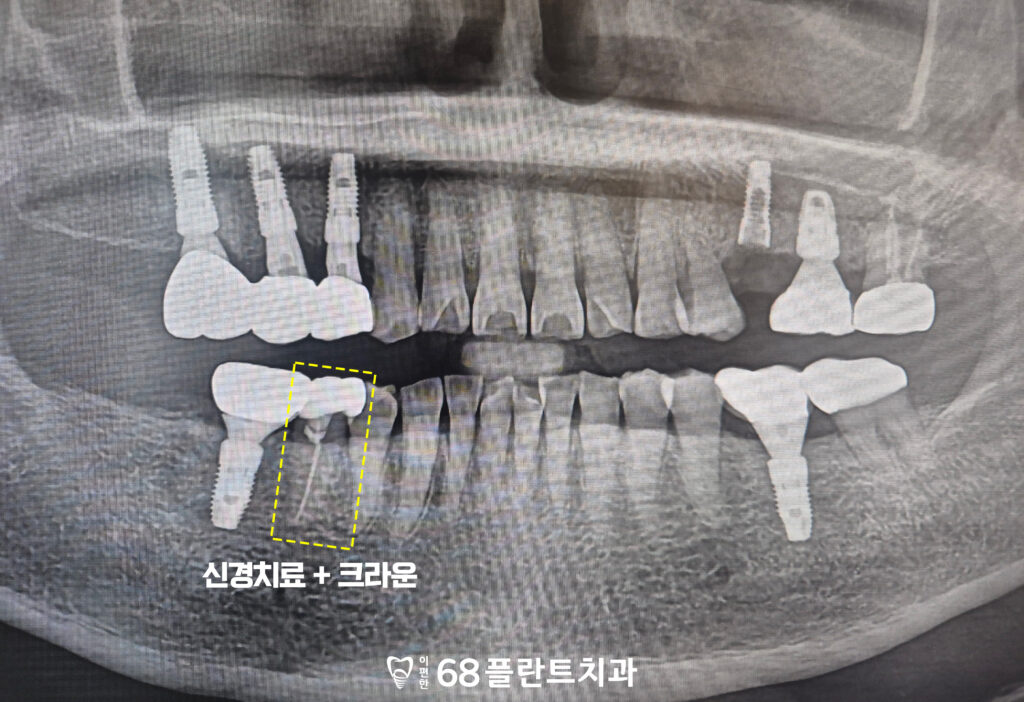

그리고 오른쪽 아래 치아는

크랙으로 인한 자극과 통증 가능성을 고려하여

신경치료를 통해 치아 내부의 염증을 제거하고,

통증을 완화한 뒤

추후 크라운 치료가 가능하도록

기초 치료를 진행하였습니다.

이후 증상이 점차 사라지고

불편함 없이 지내고 계시다고 하셔서,

해당 치아는 크라운을 제작하여

치아를 전체적으로 감싸

보호해 주는 치료를 진행하였습니다.

이를 통해 크랙의

추가 진행을 예방하고,

저작 시 부담을 줄여

안정적으로 사용할 수 있도록

마무리하였습니다.